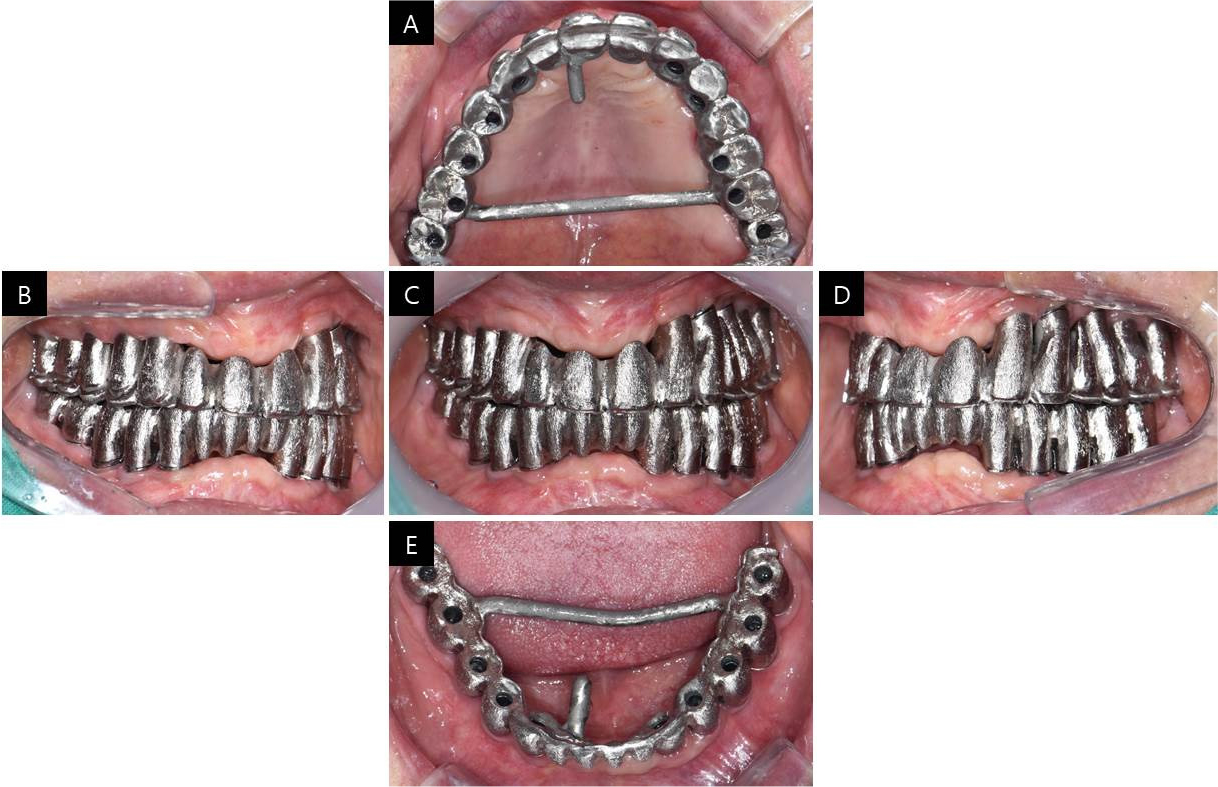

Three months after provisional restoration, a final impression was taken to make a definitive prosthesis using pick-up type impression copings that were splinted together with Pattern Resin on the second master cast that was used for provisional restoration (Fig. 3). The jaw-relation record was acquired using a lucia jig, made with temporary cylinders, and the vertical dimension was set the same as provisional restoration and former dentures. The Willis method was also used for esthetic evaluation, and TMJ checks were performed. The occlusal plane was transferred using the POP bow system, which provides information on the interpupillary line and ala to the tragus line, and then transferred to an articulator (Fig. 4).

CAD software was used to make customized abutments for a screw-cement retained prosthesis (SCRP). For better esthetics, the abutments were adjusted in the mouth for the equi-gingival margin and anodized to a gold color. A full contour wax-up was performed to fabricate the metal framework and was assayed in the mouth to check the final contours of the restoration and screw access holes (Fig. 5). To fabricate the metal framework, the wax was cut back, and the framework was cast in palladium and gold alloy, suitable for high-fusing porcelain (Fig. 6). The adaptation of the metal framework with abutments was checked with Fit Checker II (GC Corporation, Tokyo, Japan). We also confirmed that there was no muscle discomfort upon wide opening of the mouth, after which we proceeded with a one-piece metal superstructure.